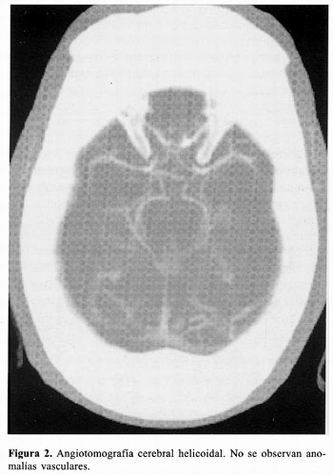

La angiotomografia cerebral helicoidal se realizó al tercer día y no se observó ninguna malformación vascular intracraneal (figura 2). La angiografía carotídea izquierda por inyección intraarterial del contraste yodado no evidenció lesiones aneurismáticas (figura 3).